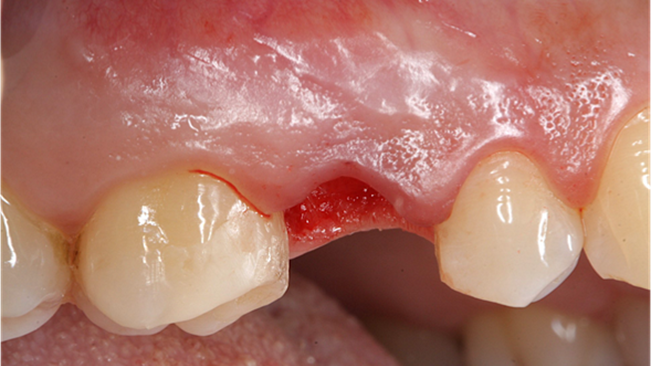

Clinical case: AnyRidge immediate loading

- Courtesy of Dr. Andres Paraud Freixas, Chile -

Keywords

AnyRidge, ISQ value, initial stability, immediate loading, KnifeThread, maxillary anterior, Mega ISQ, Dr. Andres Paraud Freixas

Products:

AnyRidge implant system, Mega ISQ, Digital prosthesis